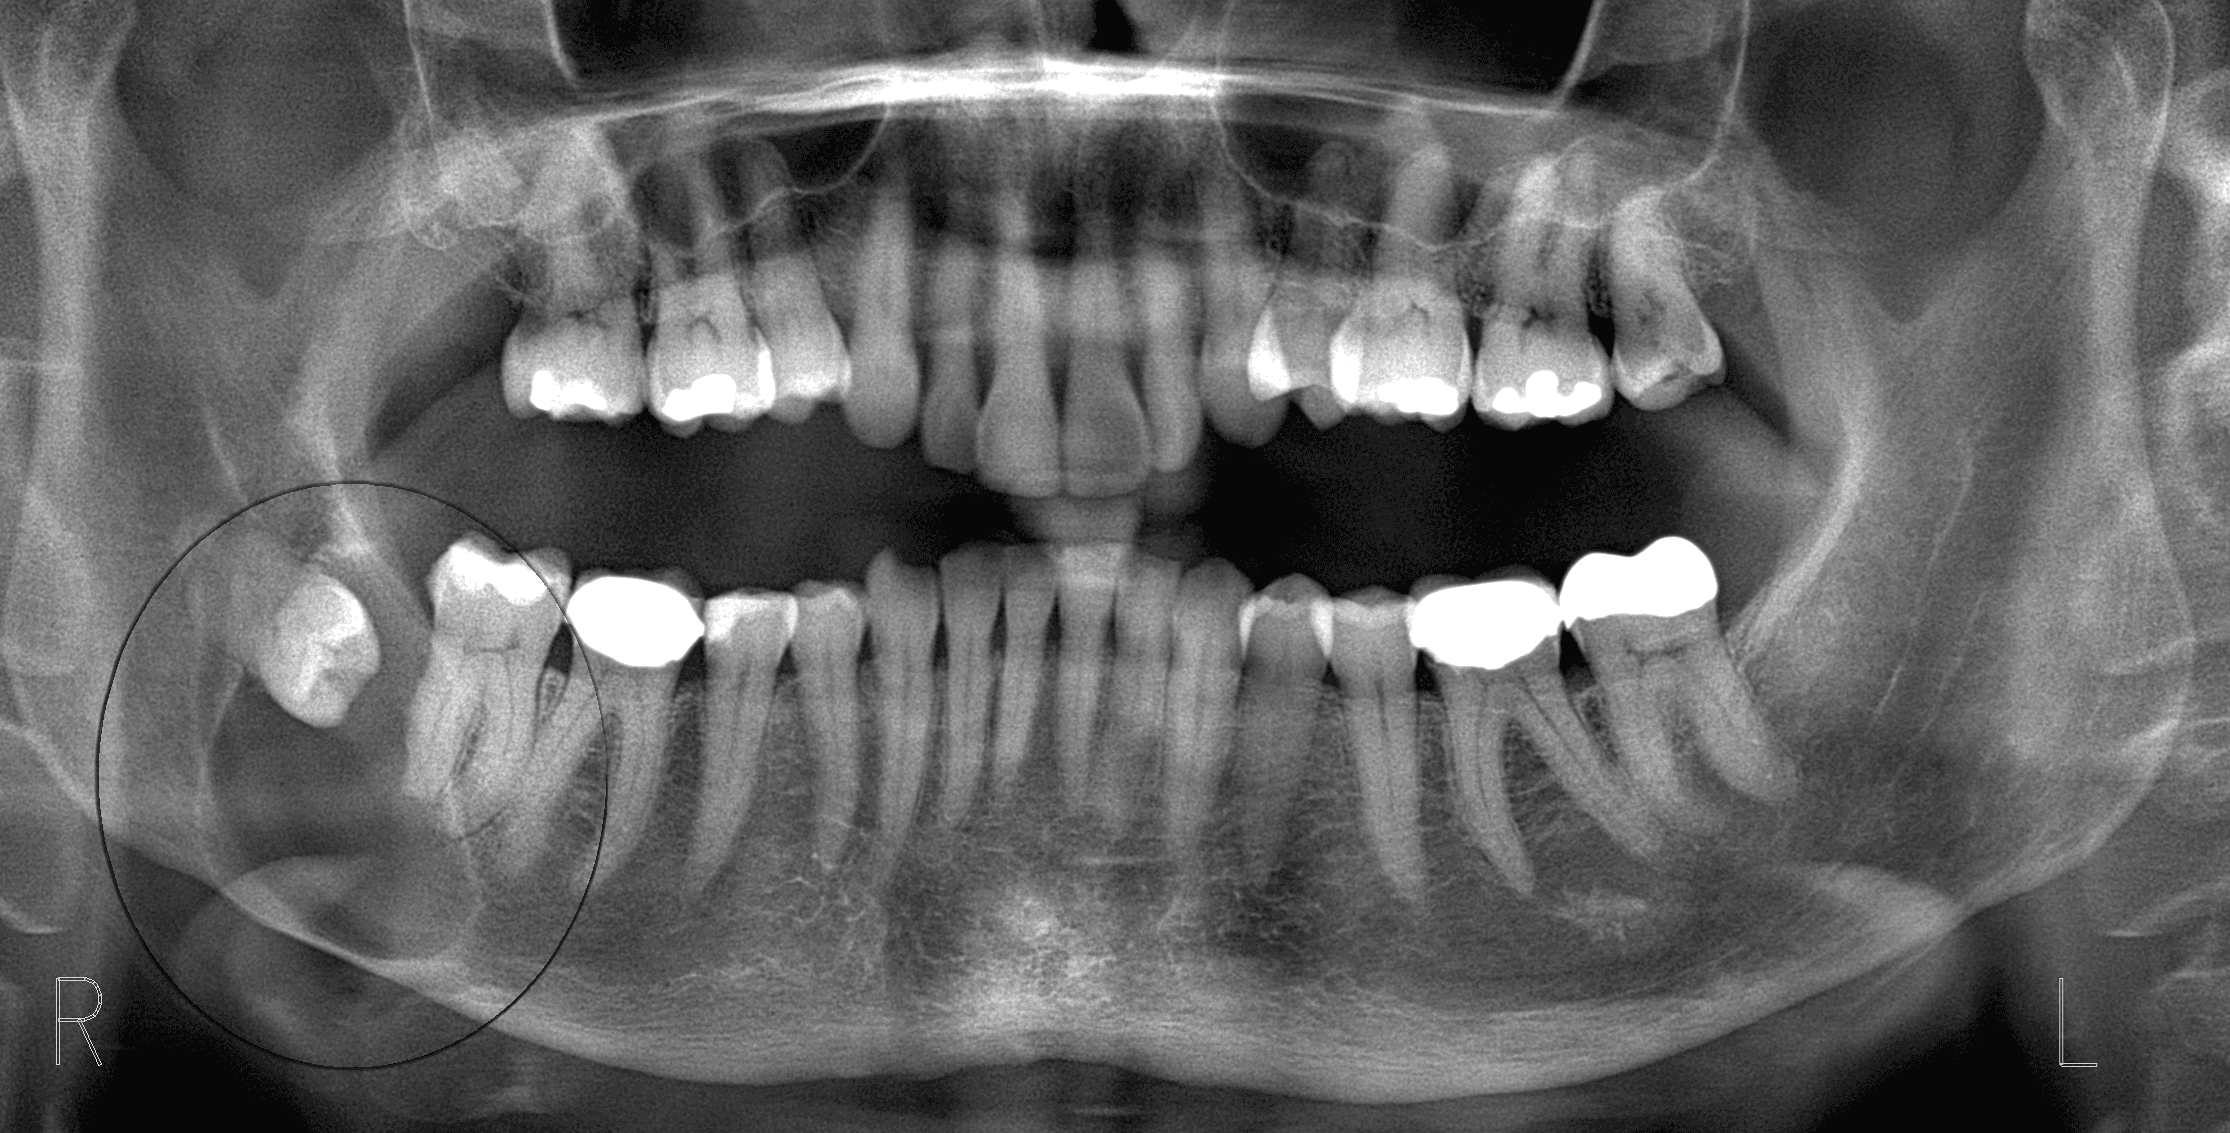

Surgery involves repairing injuries to the face, jaw and neck, addressing damage to soft tissues and bones in order to restore function, improve appearance and address psychological impacts. (Condilar fracture vs Repair of fracture)